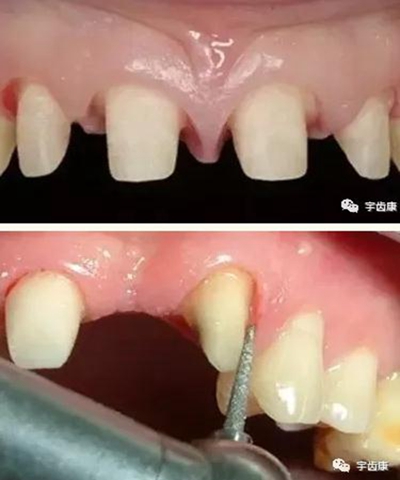

4. 預(yù)留修復(fù)體的空間

5. 邊緣的適合性

牙體各個(gè)面的解剖厚度

烤瓷牙結(jié)構(gòu)知識(shí)